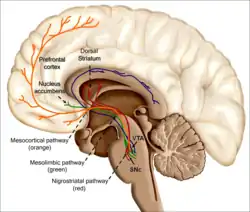

Nicotine is a parasympathomimetic stimulant[8] that binds to and activates nicotinic acetylcholine receptors in the brain,[9] which subsequently causes the release of dopamine and other neurotransmitters, such as norepinephrine, acetylcholine, serotonin, gamma-aminobutyric acid, glutamate and endorphins.[10] Nicotine interferes with the blood–brain barrier function, and as a consequence raises the risk of brain edema and neuroinflammation.[11] When nicotine enters the brain it stimulates, among other activities, the midbrain dopaminergic neurons situated in the ventral tegmental area and pars compacta.[12]

Nicotine is a parasympathomimetic stimulant[8] that binds to and activates nicotinic acetylcholine receptors in the brain,[9] which subsequently causes the release of dopamine and other neurotransmitters, such as norepinephrine, acetylcholine, serotonin, gamma-aminobutyric acid, glutamate, endorphins,[10] and several neuropeptides, including proopiomelanocortin-derived α-MSH and adrenocorticotropic hormone.[52] Corticotropin-releasing factor, Neuropeptide Y, orexins, and norepinephrine are involved in nicotine addiction.[53]

Nicotine interferes with the blood–brain barrier function, and as a consequence raises the risk of brain edema and neuroinflammation.[11] When nicotine enters the brain it stimulates, among other activities, the midbrain dopaminergic neurons situated in the ventral tegmental area and pars compacta.[12] It induces the release of dopamine in different parts of the brain, such as the nucleus accumbens, amygdala, and hippocampus.[12] Ghrelin-induced dopamine release occurs as a result of the activation of the cholinergic–dopaminergic reward link in the ventral tegmental area, a critical part of the reward areas in the brain related with reinforcement.[60] Ghrelin signaling may affect the reinforcing effects of drug dependence.[60]